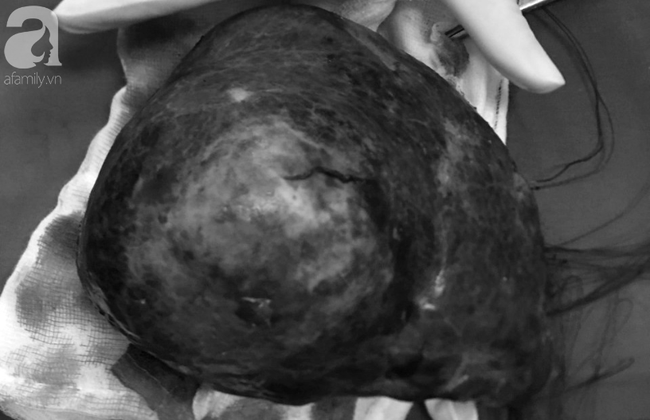

Ngày 16/12, Bệnh viện (BV) đa khoa Xuyên Á (TP.HCM) cho biết, nơi đây đã thực hiện phẫu thuật cắt bỏ khối u gan có kích thước khủng chiếm gần hết lá gan phải bệnh nhân L.V.T (63 tuổi, ngụ huyện Củ Chi, TP.HCM).

Ông T. đến khám tại BV trong tình trạng cơ thể gầy xọp, bụng trướng to. Qua khám lâm sàng, làm các xét nghiệm cận lâm sàng như siêu âm, chụp CT Scan, MRI, các bác sĩ phát hiện có khối u tại gan phải của bệnh nhân.

Khối u này khả năng ác tính, kích thước lớn chiếm gần hết gan phải.

Sau khi hội chẩn các chuyên khoa Ngoại tổng quát, Đơn vị U gan, Can thiệp tim mạch và Gây mê hồi sức, các bác sĩ thống nhất phẫu thuật cắt gan phải là cách điều trị hiệu quả nhất để giải quyết dứt điểm khối u này.

Tuy nhiên, khối u quá lớn, phần gan trái còn lại sau khi phẫu thuật sẽ không đủ đảm bảo chức năng gan. Do đó, các bác sĩ tìm cách làm cho lá gan trái (phần gan chừa lại) to lên trước khi phẫu thuật.

Tiếp đến, ca mổ cắt gan phải nhằm loại bỏ khối u gan của bệnh nhân đã được thực hiện bởi các bác sĩ Đơn vị U gan của BV.

3 tiếng phẫu thuật kéo dài, bệnh nhân đã được cắt bỏ hoàn toàn gan phải, lấy ra khối u lớn.